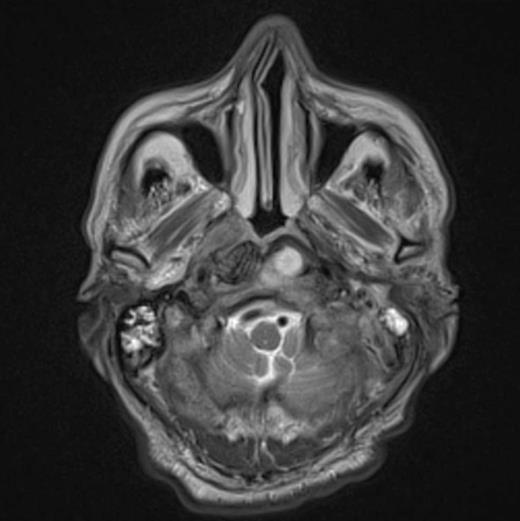

At the tertiary hospital the patient was found to be clinically wasted and weak. He also had rightward uvular deviation, absent gag reflex, weakness of the left sternocleidomastoid and trapezius, House Brackman grade 2 left facial nerve weakness and an immobile left vocal cord. This was the first time a cranial nerve examination was recorded. MRI and SPECT/CT with Gallium tracer was performed, the images acquired from which illustrate the severe extent of disease (figures 1 to 5).

He was diagnosed with MOE with extensive skull base osteomyelitis producing multiple lower cranial neuropathies. Biopsy performed by ORL/ENT surgeons grew Scedosporium apiospermum and given the extent of the infection a palliative approach was agreed upon with the patient and family.